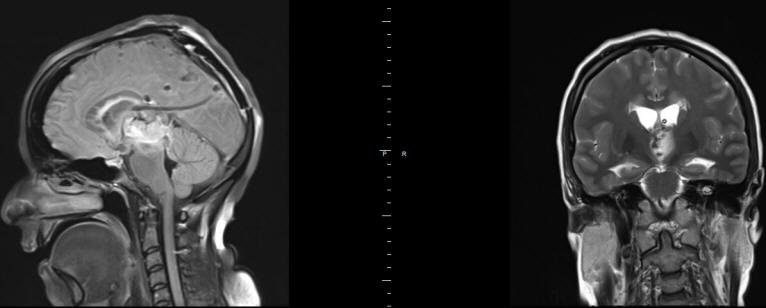

The following case demonstrate the radical resection of pituitary adenoma even with transphenoidal approach: The patient is a doctor of psychiatry 60 years old came 11-November-2015 complaining of general weakness and fainting attacks for 4 years and diagnosed as having prolactinoma. He is diabetic for 10 years with hypertension for 20 years. Signs of panhypoptuitarism were found and treated with L-thyroxin, testosterone and Dystinox 1/2 tab every 2 days. MRI sella done 29-December-2013 and repeated 14-October-2015 showing the macroadenoma is progressing in size and start to compress the optic chiasm from the left and right parasellar extension. The patient noticed visual disturbances of the left eye the last 3 months. PRL level was 6.3 µIU/ml performed 14-October-2015.

The patient was sent for investigations and MRI done 11-November-2015 showing the pituitary adenoma and the MRA showed the relation of the vascular relation to the mass.

Fig-22: The macroadenoma before surgery.

Fig-23: Intraoperative MRI confirming still having the tumor.

Fig: 24 Control MRI of the sella performed 23-December-2015 demonstrating radical resection of the pituitary adenoma. Frontal view.

Fig-25: Saggital view.